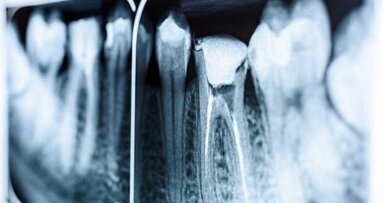

HAMBURGO, Alemanha: Um paciente anestesiado morreu após receber um tratamento de canal em um consultório de Hamburgo no mês passado. ...